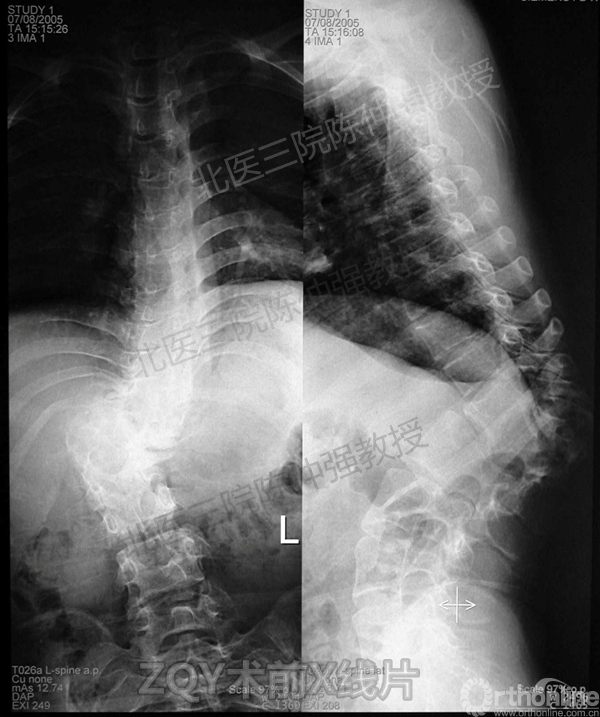

2005年,陈仲强教授在AOSpine年会上分享了一例胸腰椎陈旧结核性侧后凸畸形病例。资料如下:

患者女性17岁,胸腰椎陈旧结核性侧后凸畸形,局部呈“麻花状”扭转,无神经功能受损表现。2005年,陈仲强教授带领团队实施后路+侧前方联合入路脊柱节段切除、双轴旋转矫形术。术后患者外观显著改善,神经功能正常。术后随访证实患者截骨矫形节段骨性融合良好,矫形效果持续良好。